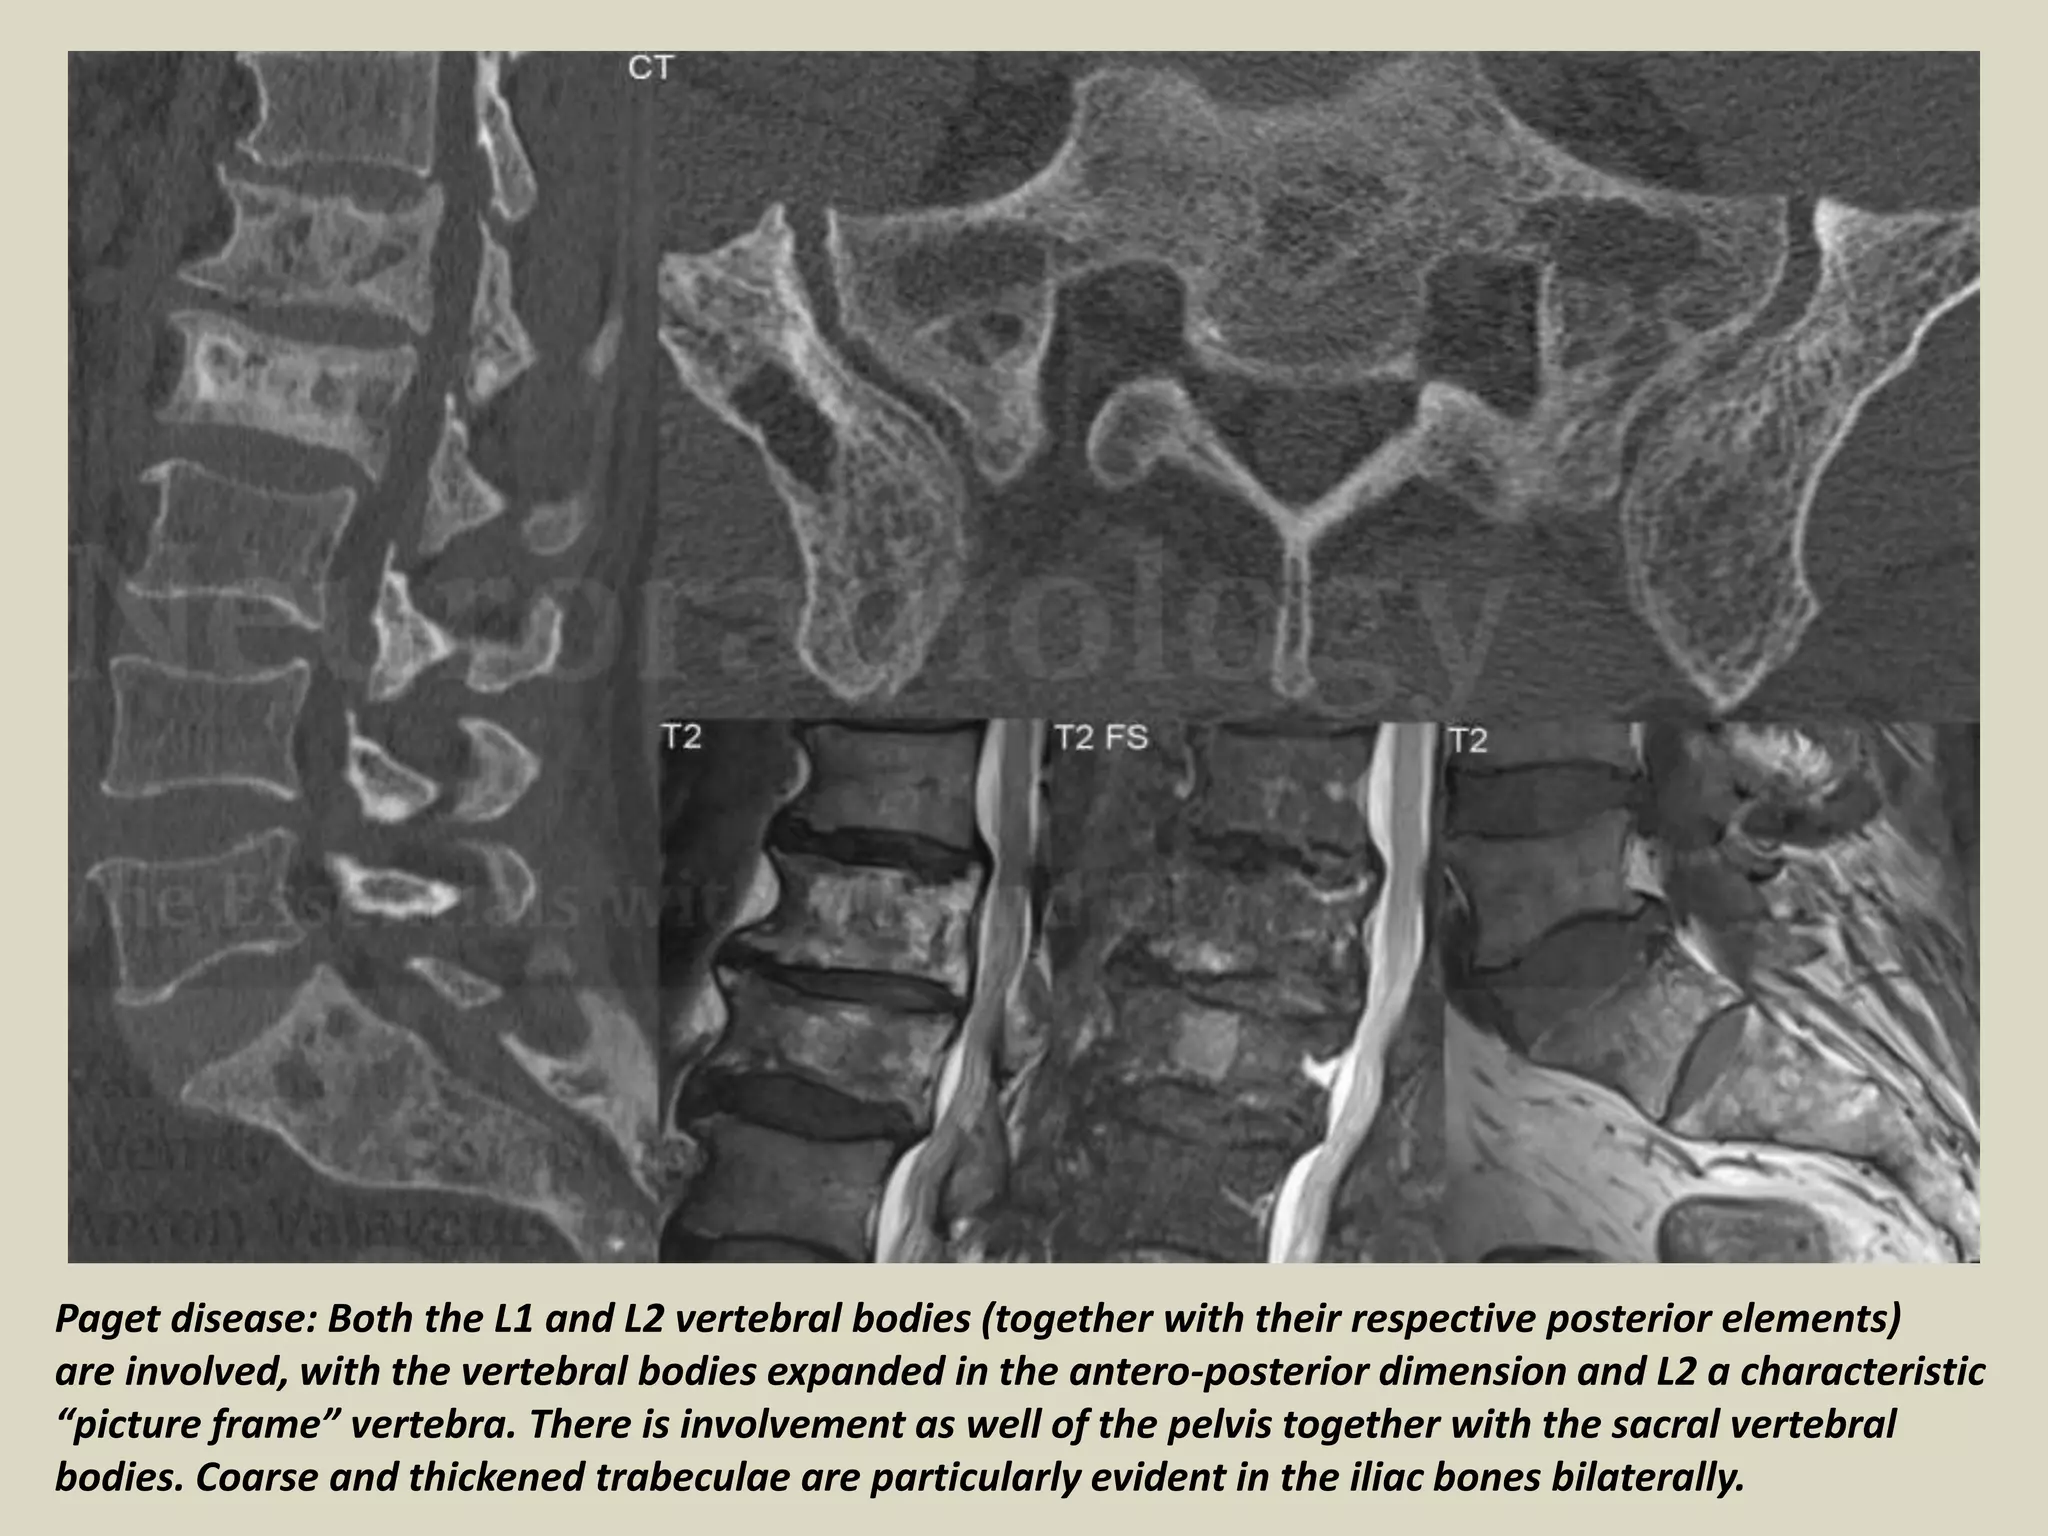

Paget disease: Both the L1 and L2 vertebral bodies (together with their respective posterior elements)

are involved, with the vertebral bodies expanded in the antero-posterior dimension and L2 a characteristic

“picture frame” vertebra. There is involvement as well of the pelvis together with the sacral vertebral

bodies. Coarse and thickened trabeculae are particularly evident in the iliac bones bilaterally.

Paget disease: Boththe L1 and L2 vertebral bodies (together with their respective posterior elements) are involved, with the vertebral bodies expanded in the antero-posterior dimension and L2 a characteristic “picture frame” vertebra. There is involvement as well of the pelvis together with the sacral vertebral bodies. Coarse and thickened trabeculae are particularly evident in the iliac bones bilaterally.